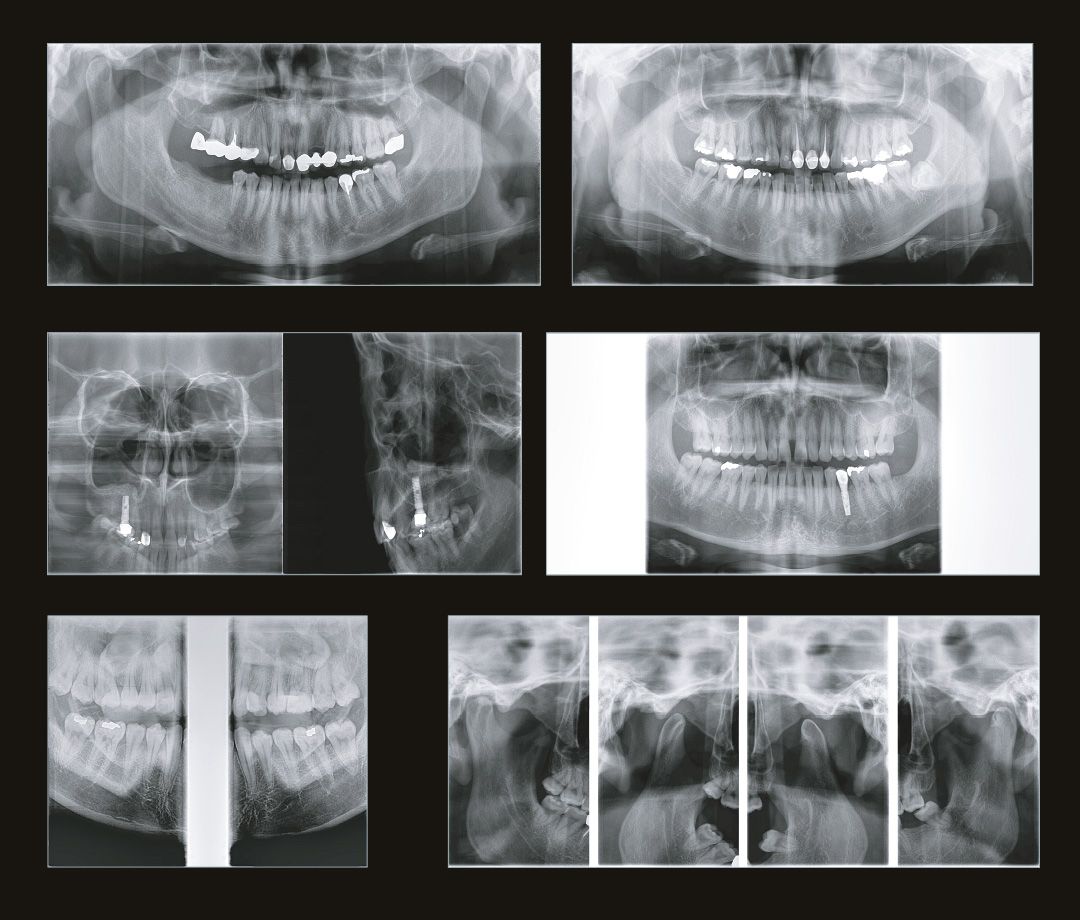

Стоматолог-терапевт по снимку видит не только кариес, а также способен оценить, как периодонтальные ткани, так и различные воспалительные процессы затрагивающие пульпарную камеру.

Стоматолог-хирург не способен производить свои манипуляции без снимка КТ, иначе он будет вынужден действовать вслепую, не сумев оценить анатомию области вмешательства.

Стоматолог-ортопед не сможет гарантировать надежность конструкции без правильной оценки стабильности опорных зубов при помощи снимка КТ.

Стоматологу-ортодонту, чтобы правильно простроить план лечения, помимо слепков, так же нужен снимок КТ.

Если же ваша стоматологическая клиника располагается в жилом доме, помимо всего написанного выше, необходимо, чтобы дентальный томограф имел мощность излучения не выше 70кВ. Современные изготовители позаботились и об этом. На рынке представлено несколько моделей, которые удовлетворяют этим требованиям. Например, модель дентального томографа Papaya 3D (Plus) от компании Genoray имеет мощность излучателя 60~69 кВ и может располагаться в жилых помещениях, не принося вред жильцам и удовлетворяя санитарно-эпидемиологическим требованиям.